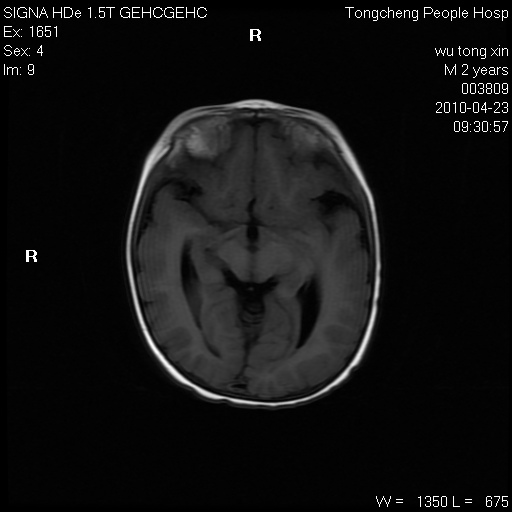

以下是引用赵物学在2010-4-25 12:43:00的发言:[br]巨脑回[br]侧脑室后角低密度影考虑hie或肾上腺脑白质营养不良?[br][br][本贴已被 赵物学 于 2010-4-25 12:51:28 修改过]

以下是引用gaoxiao在2010-4-25 16:54:00的发言:[br]巨脑回畸形。脑白质髓鞘化不良

以下是引用pujunzhi在2010-4-25 21:35:00的发言:[br]考虑 1双侧大脑皮质发育不良 2轻度脑积水 3双侧脑室后角旁片状长t1长t2信号,需继续观察,因为正常小儿此处脑白质的髓鞘化时间可以延迟到4-6岁,才显示正常。